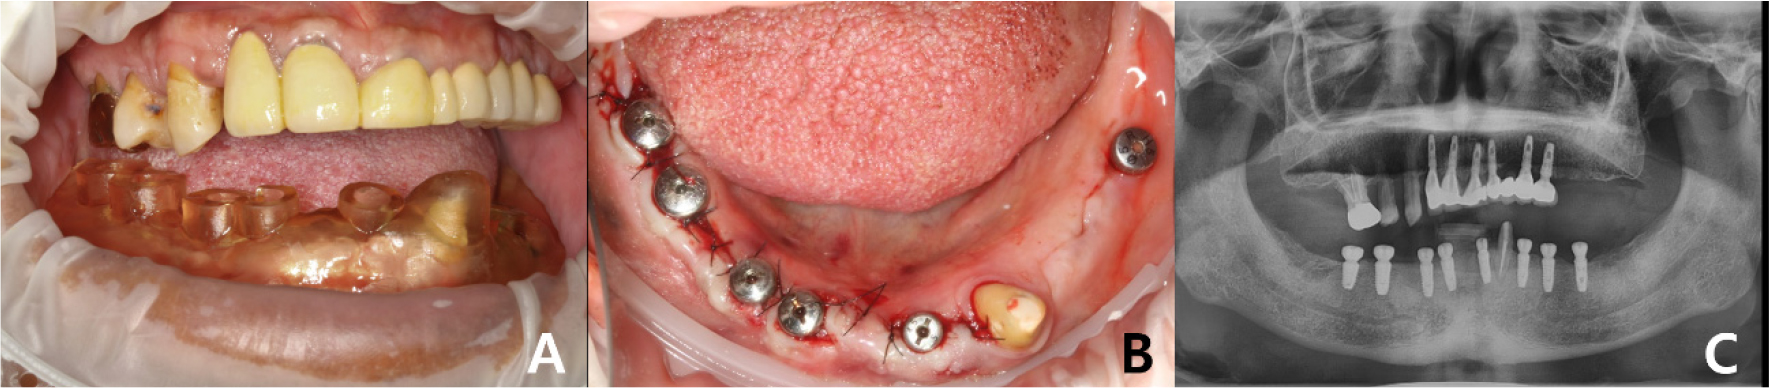

A 58-year-old male patient visited our hospital with chief complaints of missing mandibular teeth. The patient had hypertension and hyperlipidemia. Clinical and radiological examinations revealed multiple tooth loss in the mandible and canting of the maxillary teeth. The implant in the lower left second premolar area showed degree II mobility and vertical bone loss around the fixture, indicating a loss of osseointegration (Figs. 1 and 2). After removal of the dental implant on #35, implant placement was planned at sites #47, 46, 44, 43, 32, 33, 34, 36, and 37. The patient refused to undergo temporary denture placement. A radiographic stent was fabricated after bite registration using a record base, which is the conventional method for fabricating a stent in a partially edentulous jaw. CBCT was taken, and the stone model was scanned using an optical scanner (Medit T500 Dental 3D Scanner; Medit Corp., Seoul, Korea) (Fig. 3A).

Guided surgery was performed using a Dentium guide kit (XGSFK; Dentium, Seoul, Korea) for implant placement at positions #47, # 46, # 44, # 43, and # 31. To overcome the limitations of the tissue- supported guide and increase accuracy, the tops of the implants and crest levels were checked through minimal flap formation (Fig. 7). After implant placement, CBCT was taken, and the DICOM file was registered in the implant planning software (DentiqGuide; 3D Industrial Imaging Co.,Ltd., Seoul, Korea), and automatically calculated error values were obtained through the ‘pre- and post-operative analysis’ function in the software (Table 1).